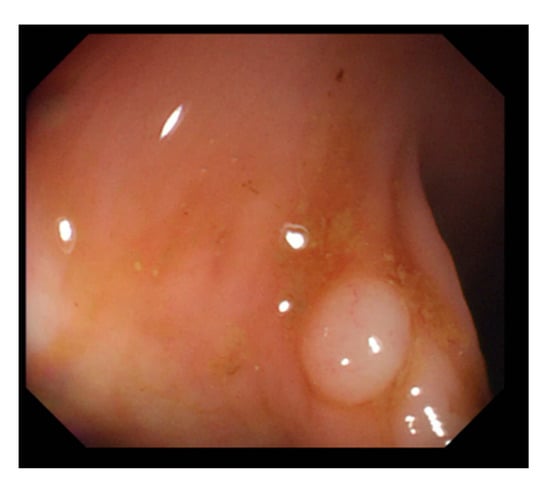

Figure 13.

Nonobvious polyp protrusions or similar to intestinal wall.

For polyp detection, the mean accuracy of grayscale images was 95.1%, which was higher than that of RGB/NBI images (94.1%). Detection errors in RGB images were caused when polyp protrusions were nonobvious or had a texture similar to that of the intestinal wall (Figure 13), images had excessive noise (Figure 14), or the polyps had an excessively small pixel size (Figure 15). Particularly, polyps with a size less than 1600 pixels (40 × 40 pixels) in the image were likely to be misjudged. Therefore, we recommend that in polyp detection, the length and width of polyp images must be at least 40 pixels in the lens regardless of the actual size of the polyps. This is likely to reduce misjudgment. We also found that when the colorectal polyps image is more complex, such as with more wrinkles or light spots, the use of color image deep learning for polyp detection may be more accurate. In addition, when the vascular lines of colorectal polyps were less obvious, such as unfocused or residual images, it would be better to use gray-scale image deep learning for polyp detection. Next step we plan to use a hybrid deep learning model that combines color and grayscale images for polyp detection in the dynamic colonoscopy videos. Maybe it can take the advantages of both methods as well as improve the detection accuracy.